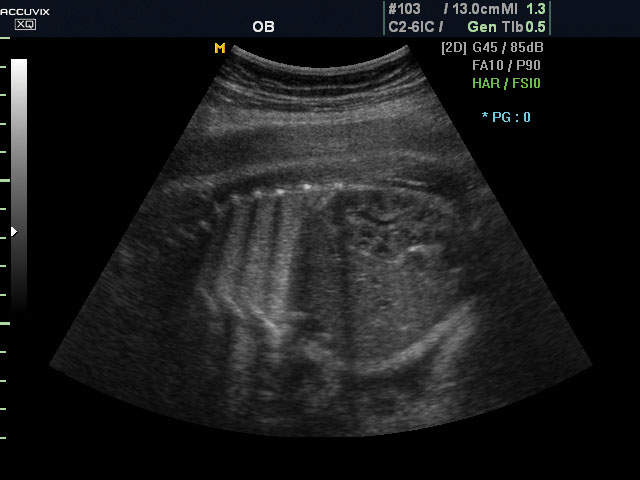

A pontos analízis és diagnózis iránti egyre növekvő igény kiszolgálására a MEDISON egy új real time képfeldolgozó technológiát fejlesztett ki Dynamic MR™ elnevezéssel. Az eljárás a diagnosztikus ismeretanyagot a precizitás és a pontosság egy teljesen új szintjére emeli. Használata az alapvető 2D ultrahang képinformáció real time, kivételesen kristálytiszta és kiemelkedően részletezett megjelenítését teszi lehetővé tűéles kontúrok és finoman rajzolt szövetstruktúra mellett. A DMR™  technológia ideális eszköze az ultrahang-diagnosztikának kezdve a szülészet-nőgyógyászattól a foetalis echon át az általános alkalmazásokig.

Magzati koponya képe normál 2D módbanMagzati koponya 2D képe bekapcsolt Dynamic MR funkcióvalMagzat törzsének képe normál 2D módbanMagzat törzsének képe bekapcsolt Dynamic MR funkcióvalMagzat felsőajakjának és orrának képeMagzat felsőajakjának és orrának képe bekapcsolt Dynamic MR funkcióval

A DynamicMR alkalmazása az átlagos ultrahang teljesítményt a zaj és szemcsézettség jellegű műtermékek kiszűrése révén a vizuális diagnosztika, a precizitás és a pontosság új szférájába emeli. Figyelje meg a cerebellum, CSP és cisterna magna élstruktúráit, mennyire pontosan definiáltak és a teljes agyi struktúra ábrázolása a Dynamic MR alkalmazásával milyen látványosan javul.